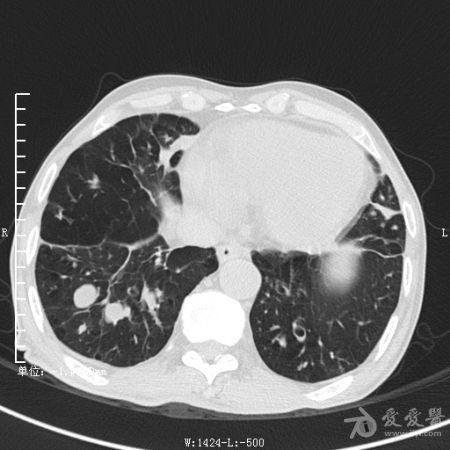

典型支气管扩张及肺水肿CT片

典型支气管扩张肺水肿